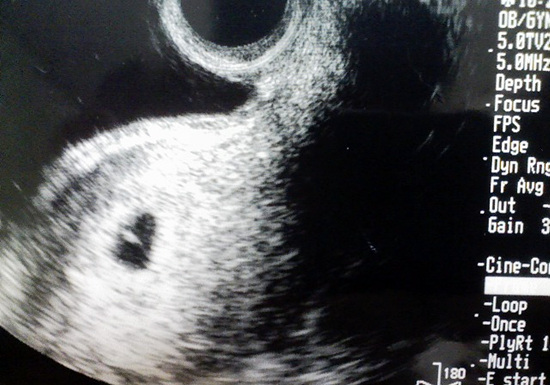

▲ 2005년 4월 20일. 큰 아이 미우가 처음으로 세상에 모습을 드러낸 날

이미 짐작했기 때문에 담담했다. 미와코는 진찰대에서 일어나자마자 긴장된 표정으로 물었다.

"건강한가요?"

의사는 건조하고 짧게, 그러나 단호하게 답했다.

"네. 건강합니다. 아주."

상식적으로 본다면 말도 안된다. 검은 점이 찍혀있고 그 안에 하얀 타원형이 아이라고 하는데 그것만 보고 건강한지 아닌지 어떻게 안단 말인가. 그런데도 미와코는 '건강한지'를 물어봤고, 의사 선생도 마치 보조를 맞추듯 '건강하다'고 말한다. 그것도 '아주'라는 수식어를 붙여 가며.

하지만 미와코는 그 말에 얼굴이 활짝 펴 졌다. 진찰실을 나오면서 몇 번이고 자기 배를 쓰다듬는다. 사진도 몇 번이고 들여다 본다. 나에게도 강조한다.